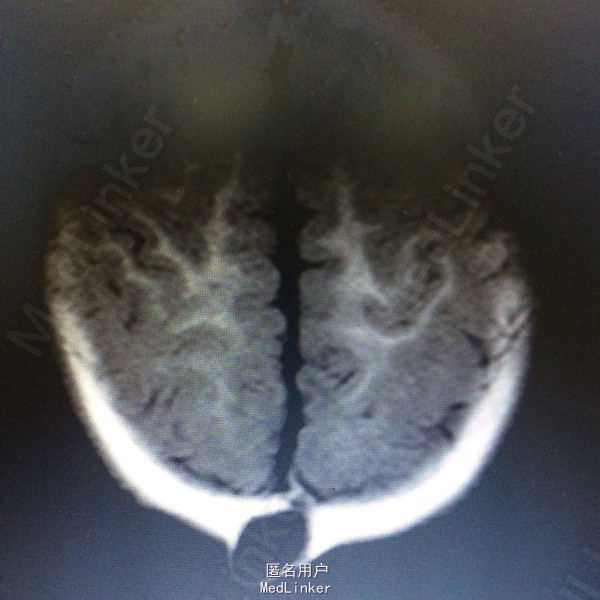

主诉:发现枕部肿块7个月 病史:患儿7月男婴,出生后即被家人发现枕后部肿物,大小约1cm*1cm*1cm,边界清楚,质软,表面光滑,挤压时患儿无哭闹等。

查体:枕后部肿物 辅助检查:行头颅MR提示顶针部中线异常信号,多考虑脑膜膨出

诊断:脑脊膜膨出 处理:枕部脑膜膨出囊切除术➕硬脑膜修补术